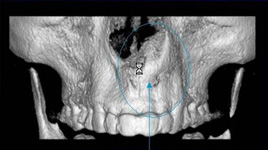

Je speciální zubní digitální tříprostorový tomograf (3D), který umožňuje na základě jediného snímkování vytvořit všechny typy RTG zobrazení, které jsou pro lékaře potřebné. Díky používané technologii tzv. „kuželového paprsku“ a speciálním senzorům je výrazně zmenšená dávka záření - o více jak 80% proti klasickému CT vyšetření. To je významné zejména u dětí. Pomocí tohoto přístroje je možné zjisti skutečnou situaci v čelistních kostech pacienta tedy množství kosti - můžeme změřit skutečnou šířku i výšku kosti, i kvalitu kosti (hustotu) v místě uvažované implantace. 3D (tříprostorové) zobrazení umožňuje zvýšit prostorovou představu operatéra ještě před vlastní operací a zároveň pacientovi lépe objasnit a ukázat oblast plánovaného zavedení implantátu.

Pacient „neumí číst“ RTG snímky, ale díky 3D zobrazení vidí „svoji skutečnou čelist“ - např. jak je nízká či úzká, vidí průběh nervu nebo velikost čelistní dutiny, což mu umožní i pochopení nutnosti v některých případech provést pomocné zákroky ještě před vlastním zavedením implantátu (viz. kostní štěp, sinus lift, kostní granulát...).

Vyšetření pomocí tohoto přístroje používáme i ve stomatochirurgii (zlomeniny čelistí, zuby moudrosti, cysty, onemocnění čelistního kloubu), ortodoncii (retinované zuby, nadpočetné zuby), parodontologii atd.